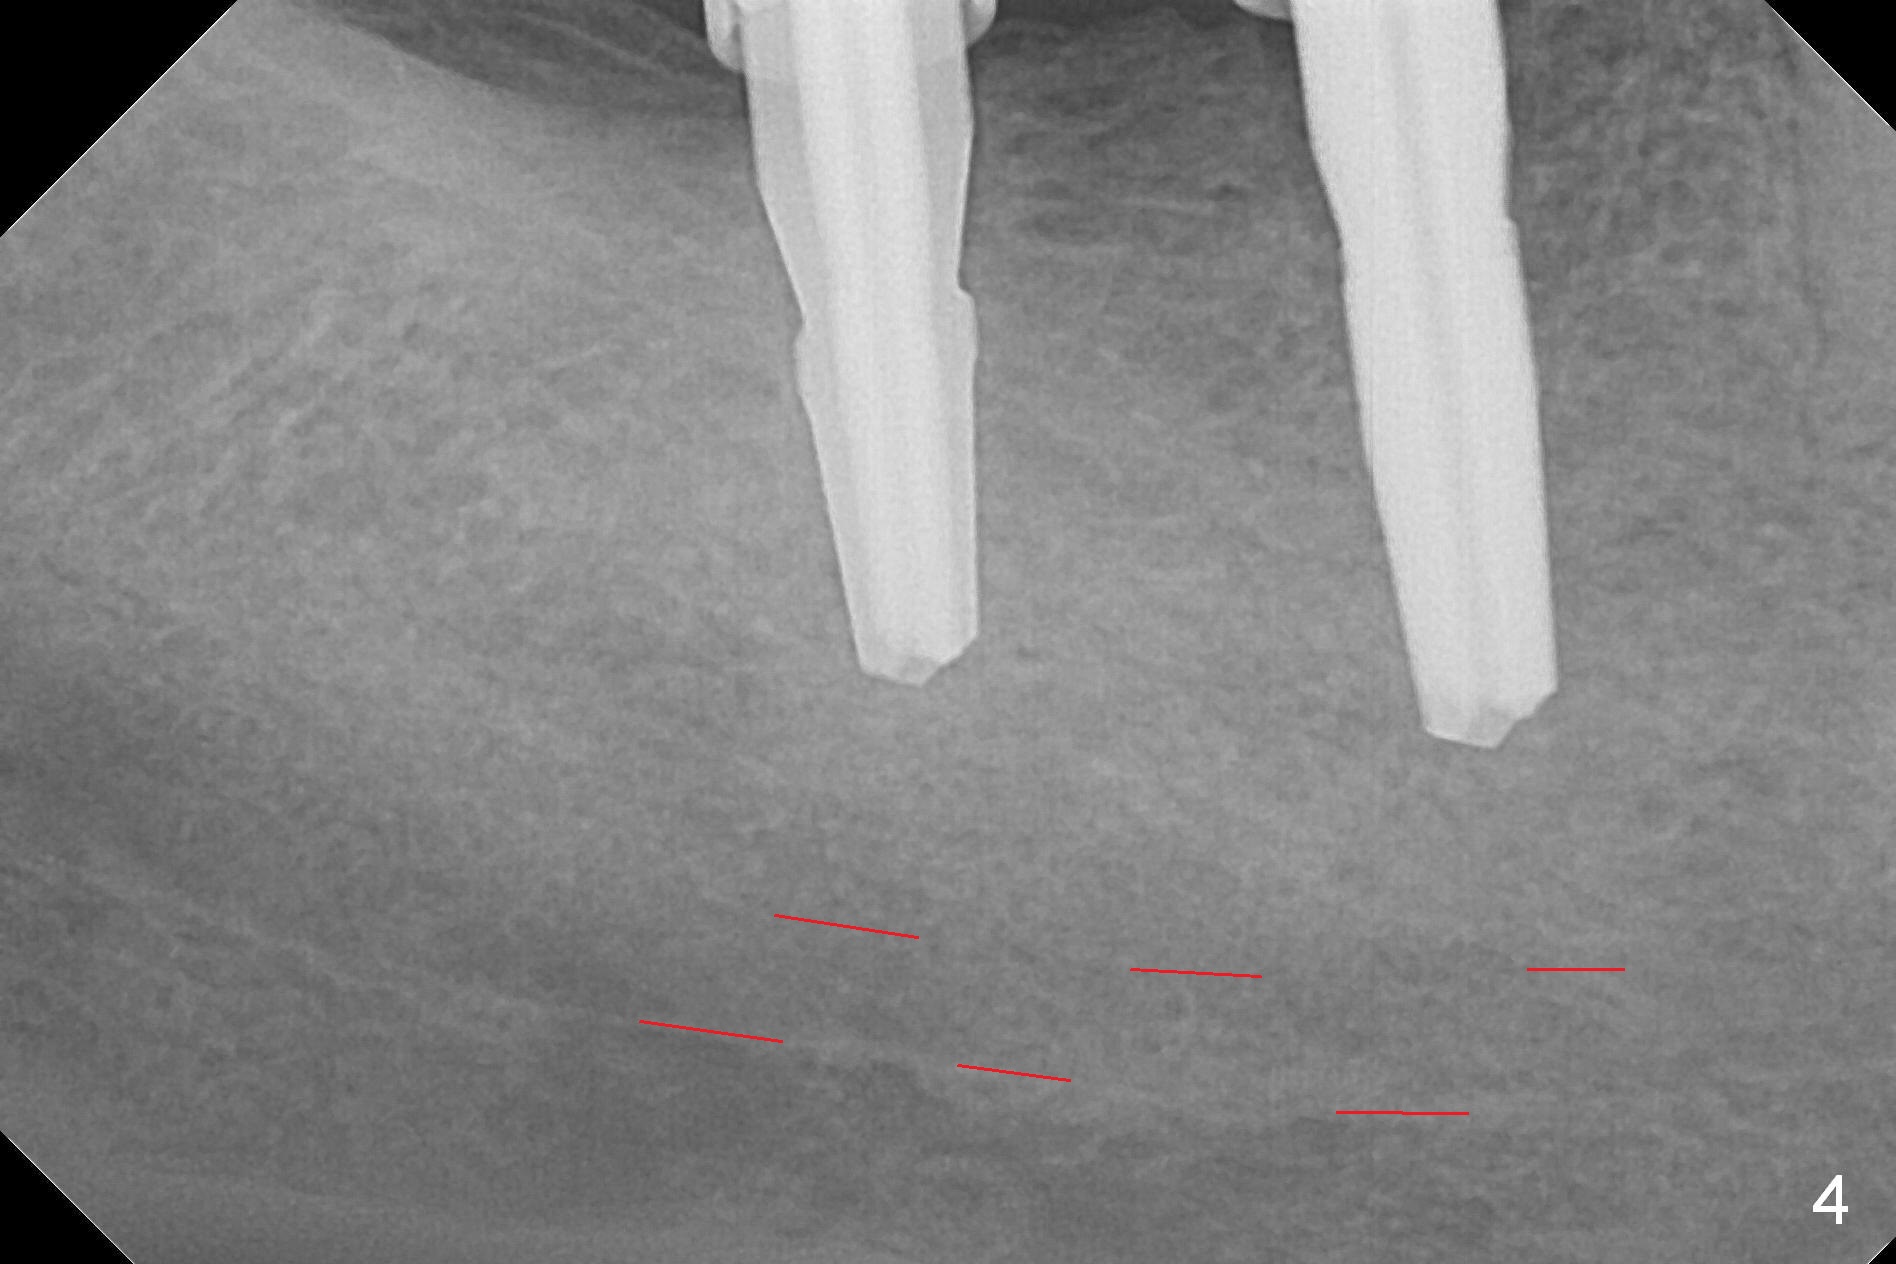

The supraerupted tooth #2 is adjusted using the lower right surgical stent. Osteotomies are initiated by using starter drill through surgical stent over the ridge (Fig.1) prior to incision. The initial depths are 10 and 12 mm at the sites of #31 and 30, respectively (Fig.2). The new sensor with the existing sensor holder cannot reach the deep portion of the lingual vestibule (Fig.2,3). Without the sensor holder, the #2 sensor with rounded corners has no problem showing the Inferior Alveolar Canal (Fig.4 red dashed line). The two implants (5x12 and 5x14 mm, Fig.5) are placed with >50 Ncm. Cemented abutments are immediately placed (6.8x4(2) and 6.8x4(3) mm) to reduce suture tension (after autogenous bone graft and collagen dressing) and hold periodontal dressing in place. The wound does not heal completely 15 days postop (Fig.6). The patient reveals that he smokes 1/2 pack per day. There is crestal bone resorption 4 months postop (Fig.7 *). It appears that for smokers, implants should be smaller, placed deeper and buried. In addition, his oral hygiene is not good.